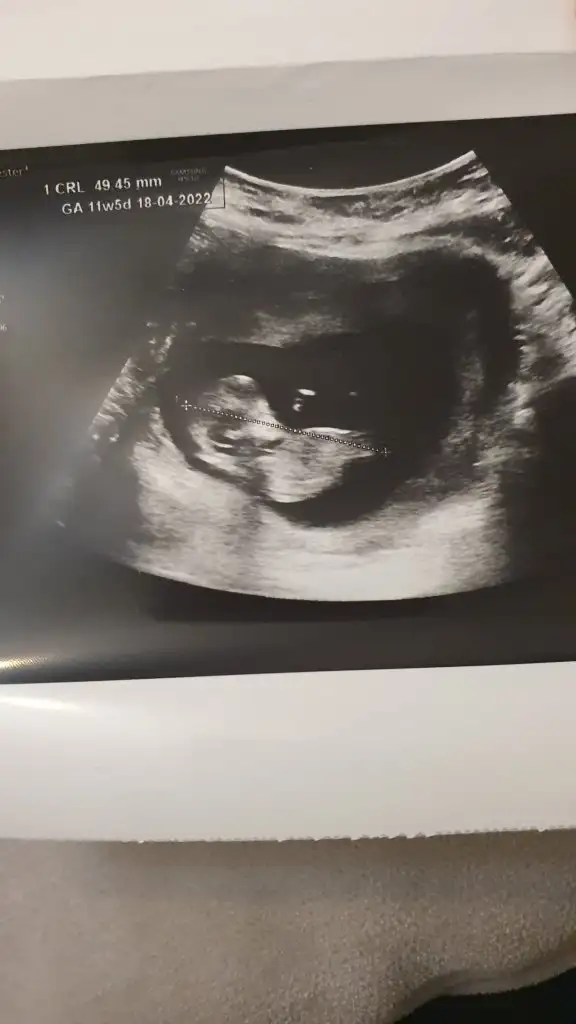

Doktor cinsiyet için erken dedi söylemedi ama ben çok merak ediyorum bakar mısınız

Merhaba arkadaşlar 11 haftalık ultrason görüntüsü, çookk merak ediyorum yorumlayabilir misiniz :))